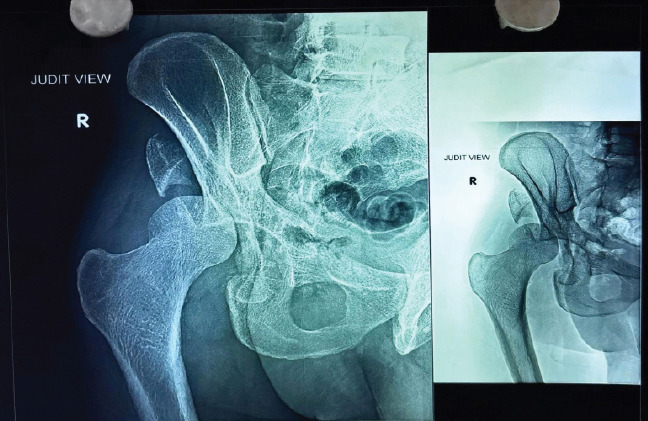

Case report: We report a case of a 42-year-old male with a chronic posterior dislocation of the right hip and a comminuted posterior wall and column acetabular fracture, presenting 2 months post-injury. The patient had previously undergone a right-sided patellectomy. Surgical intervention included THA with acetabular cage reconstruction due to segmental bone loss. At 6-month follow-up, the patient achieved pain-free ambulation, a stable prosthesis, and satisfactory functional outcomes.